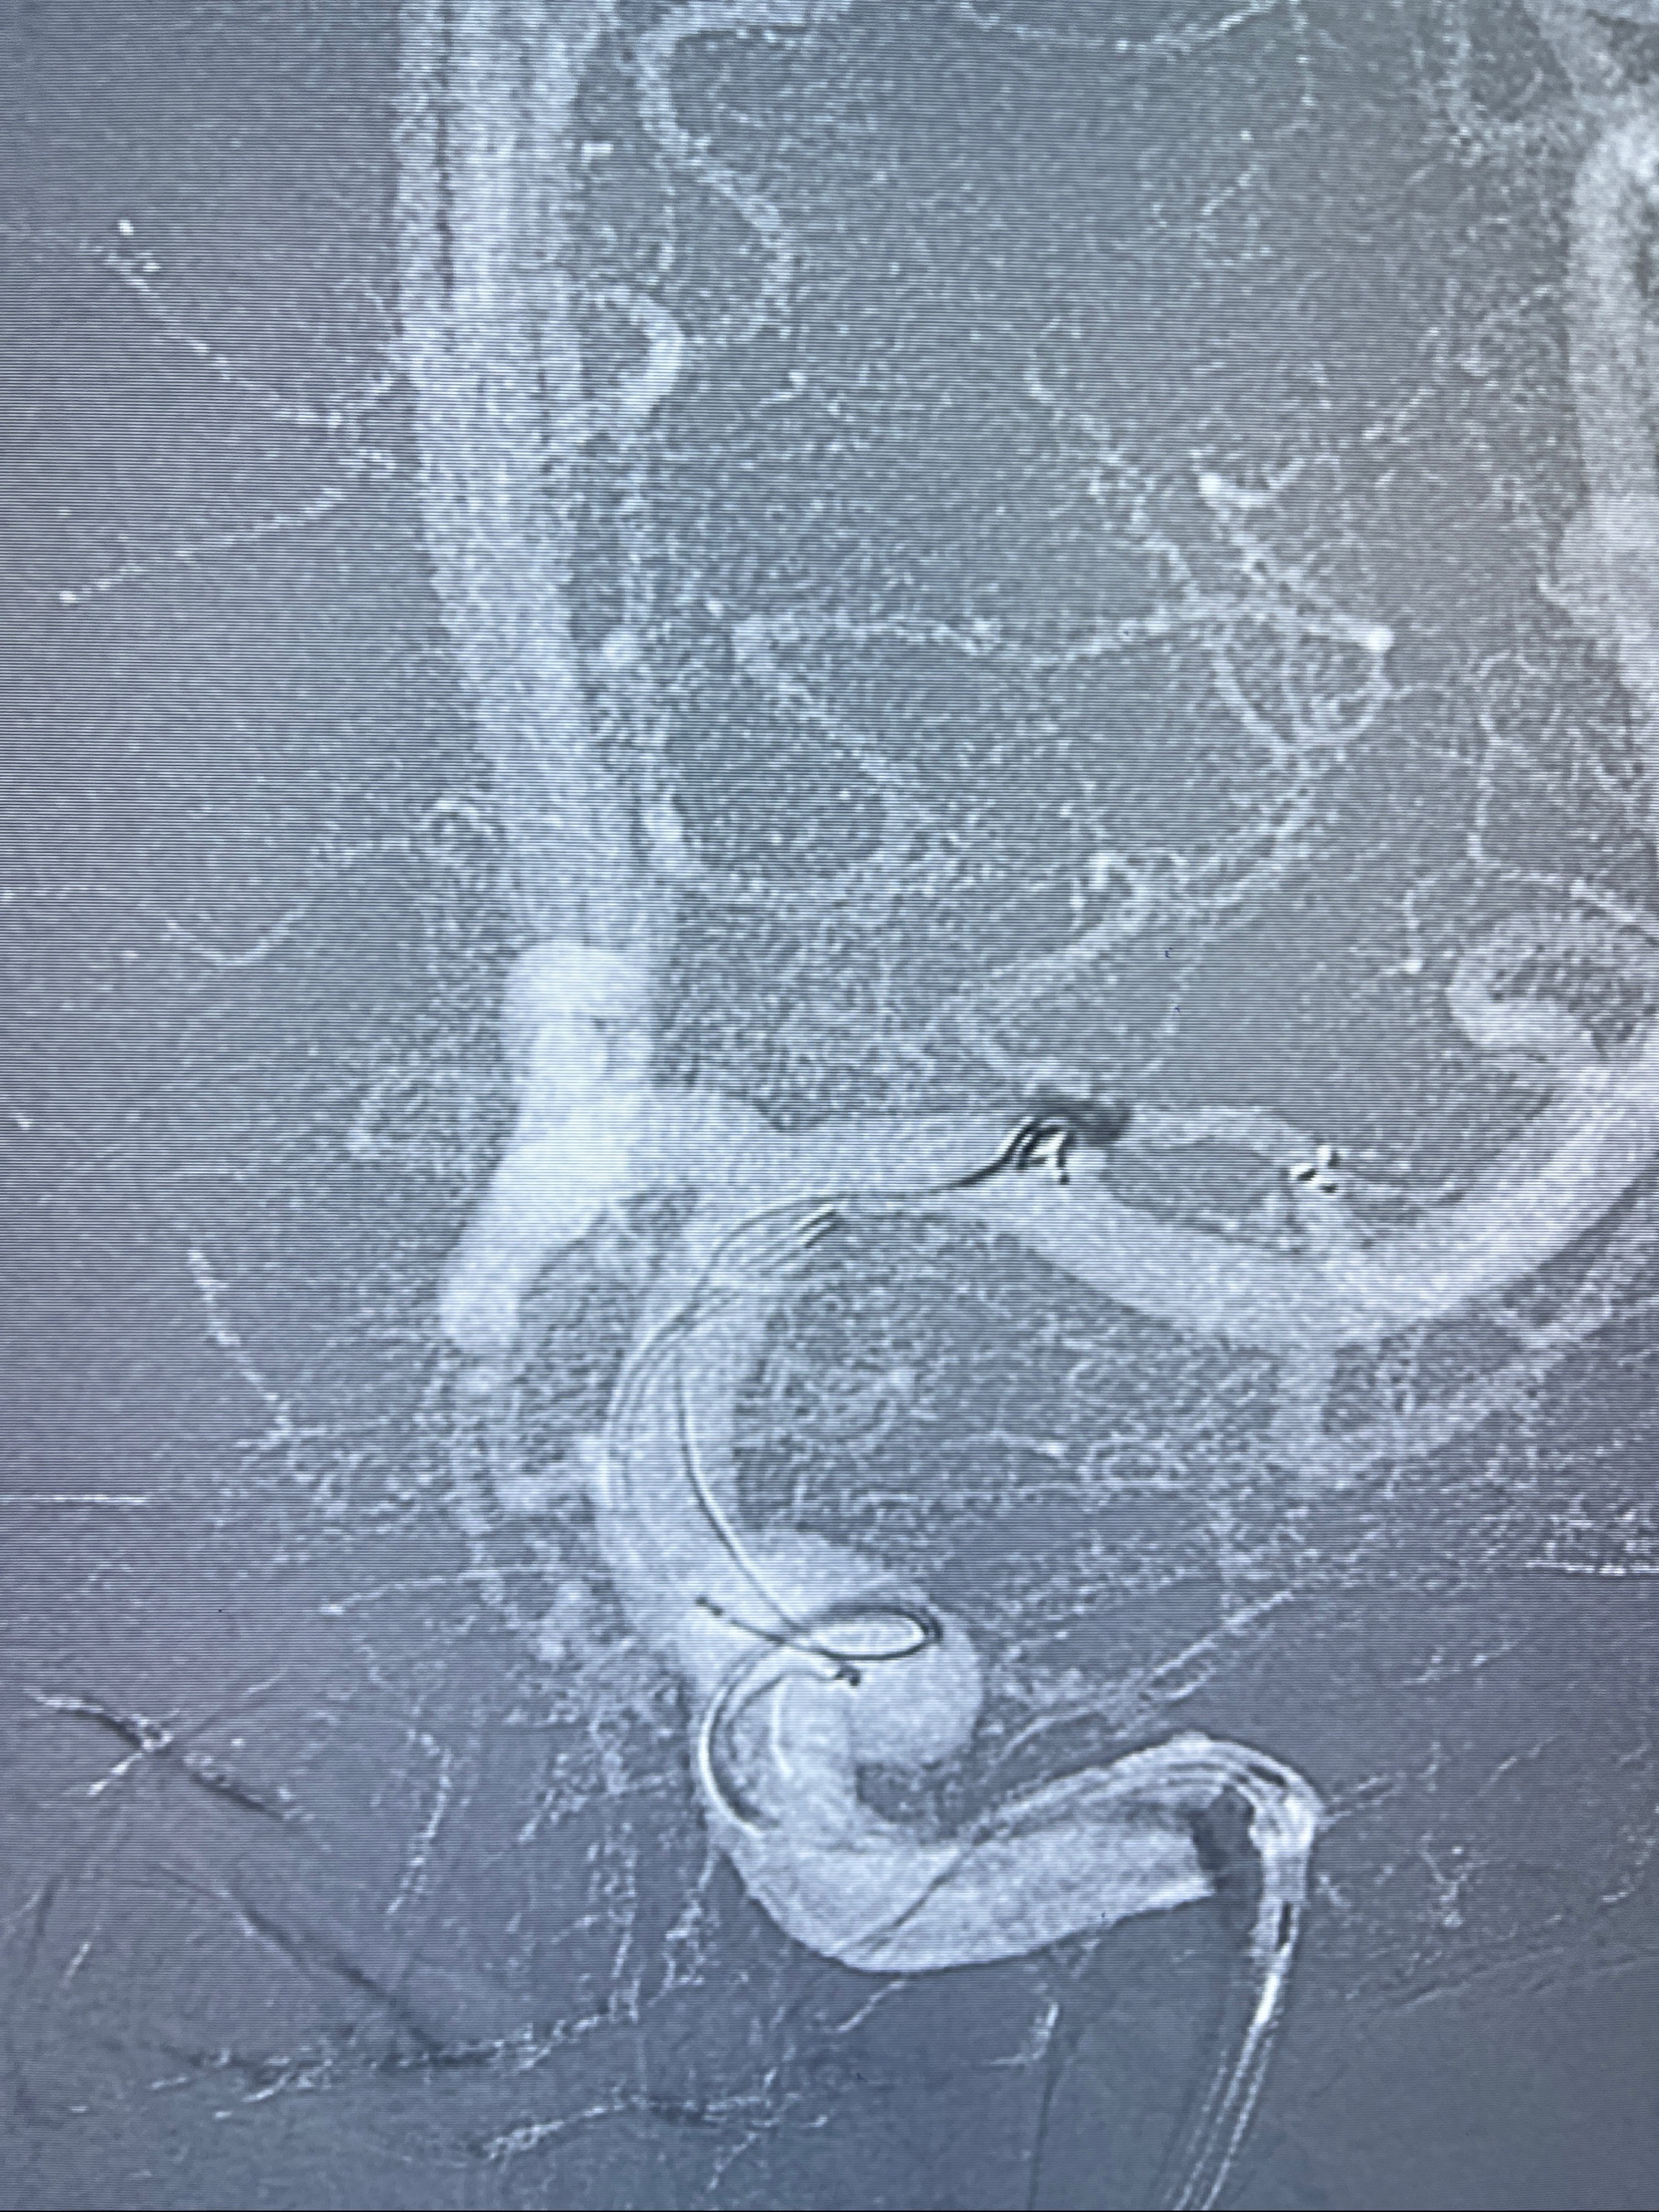

2023-08-14DSA:

左侧大脑中动脉动脉瘤,约2.6-2.8-3.4-2mm大小(瘤颈部、瘤体部、瘤高)

1.左侧大脑中动脉动脉瘤,约2.6-2.8-3.4-2mm大小(瘤颈部、瘤体部、瘤高)

2.外科手术夹闭or介入支架辅助栓塞

麻醉苏醒佳,遵嘱动作

术后即刻CT